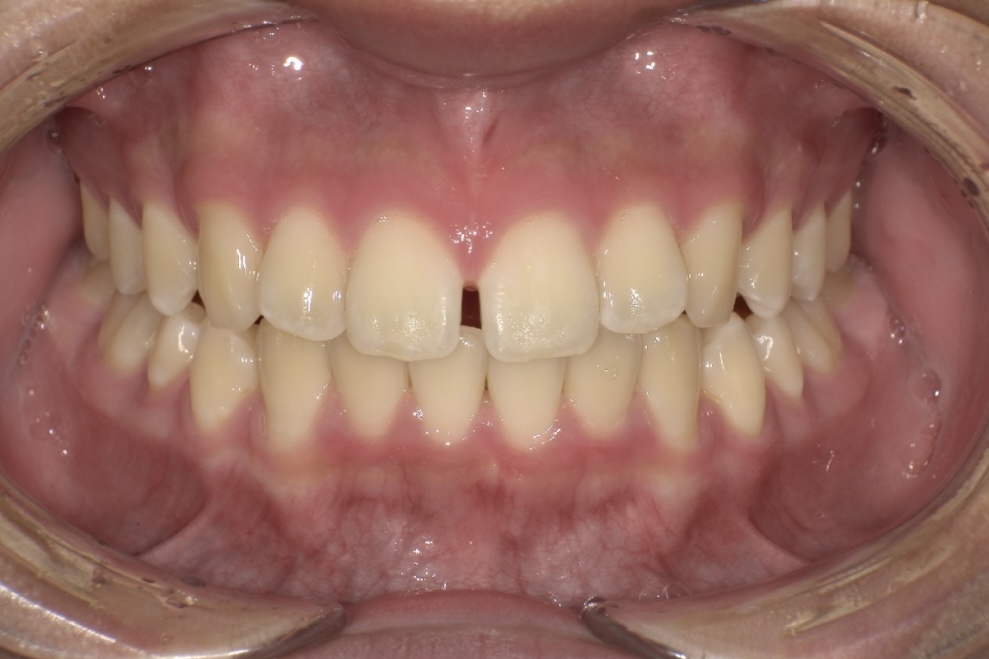

高校生の男性の患者さまで「すきっ歯」を主訴にご相談に来院されました。

治療では、見た目の改善だけでなく、成長期にあることを考慮しながら歯列全体のバランスを整えていきました。

治療期間は1年半で、すき間が改善され、口元の印象が大きく変化しています。

BEFORE

| 年齢・性別 | 高校生男性 |

|---|---|

| 主訴 | すきっ歯が気になる |

| 施術内容 | 歯全体のマウスピース矯正システム「インビザラインフル」を用いた治療 |

| 治療期間 | 1年半 |

| 費用 | 924,000円(税込) |

| リスク/副作用 | 全ての方で、疼痛、咬合痛、歯根吸収、歯肉退縮、歯髄壊死が生じる可能性があります。 |

| その他注意点 | 指定した時間、マウスピースをつけていただけない場合は治療期間が長くなる場合があります。 |